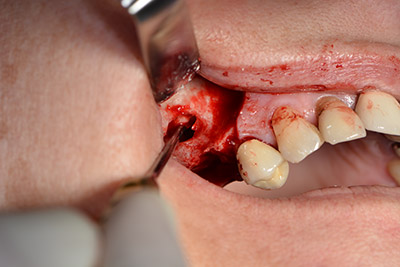

Procedura chirurgica per l'impianto

L'incisione classica (rilascio crestale e buccale) e la preparazione del lembo mucoperiosteo favoriscono un'ottima panoramica.

In questo caso vengono usati impianti di tipo SKY (bredent). Il loro protocollo chirurgico specifica una perforazione pilota di circa 1200 rpm (fig. 9).